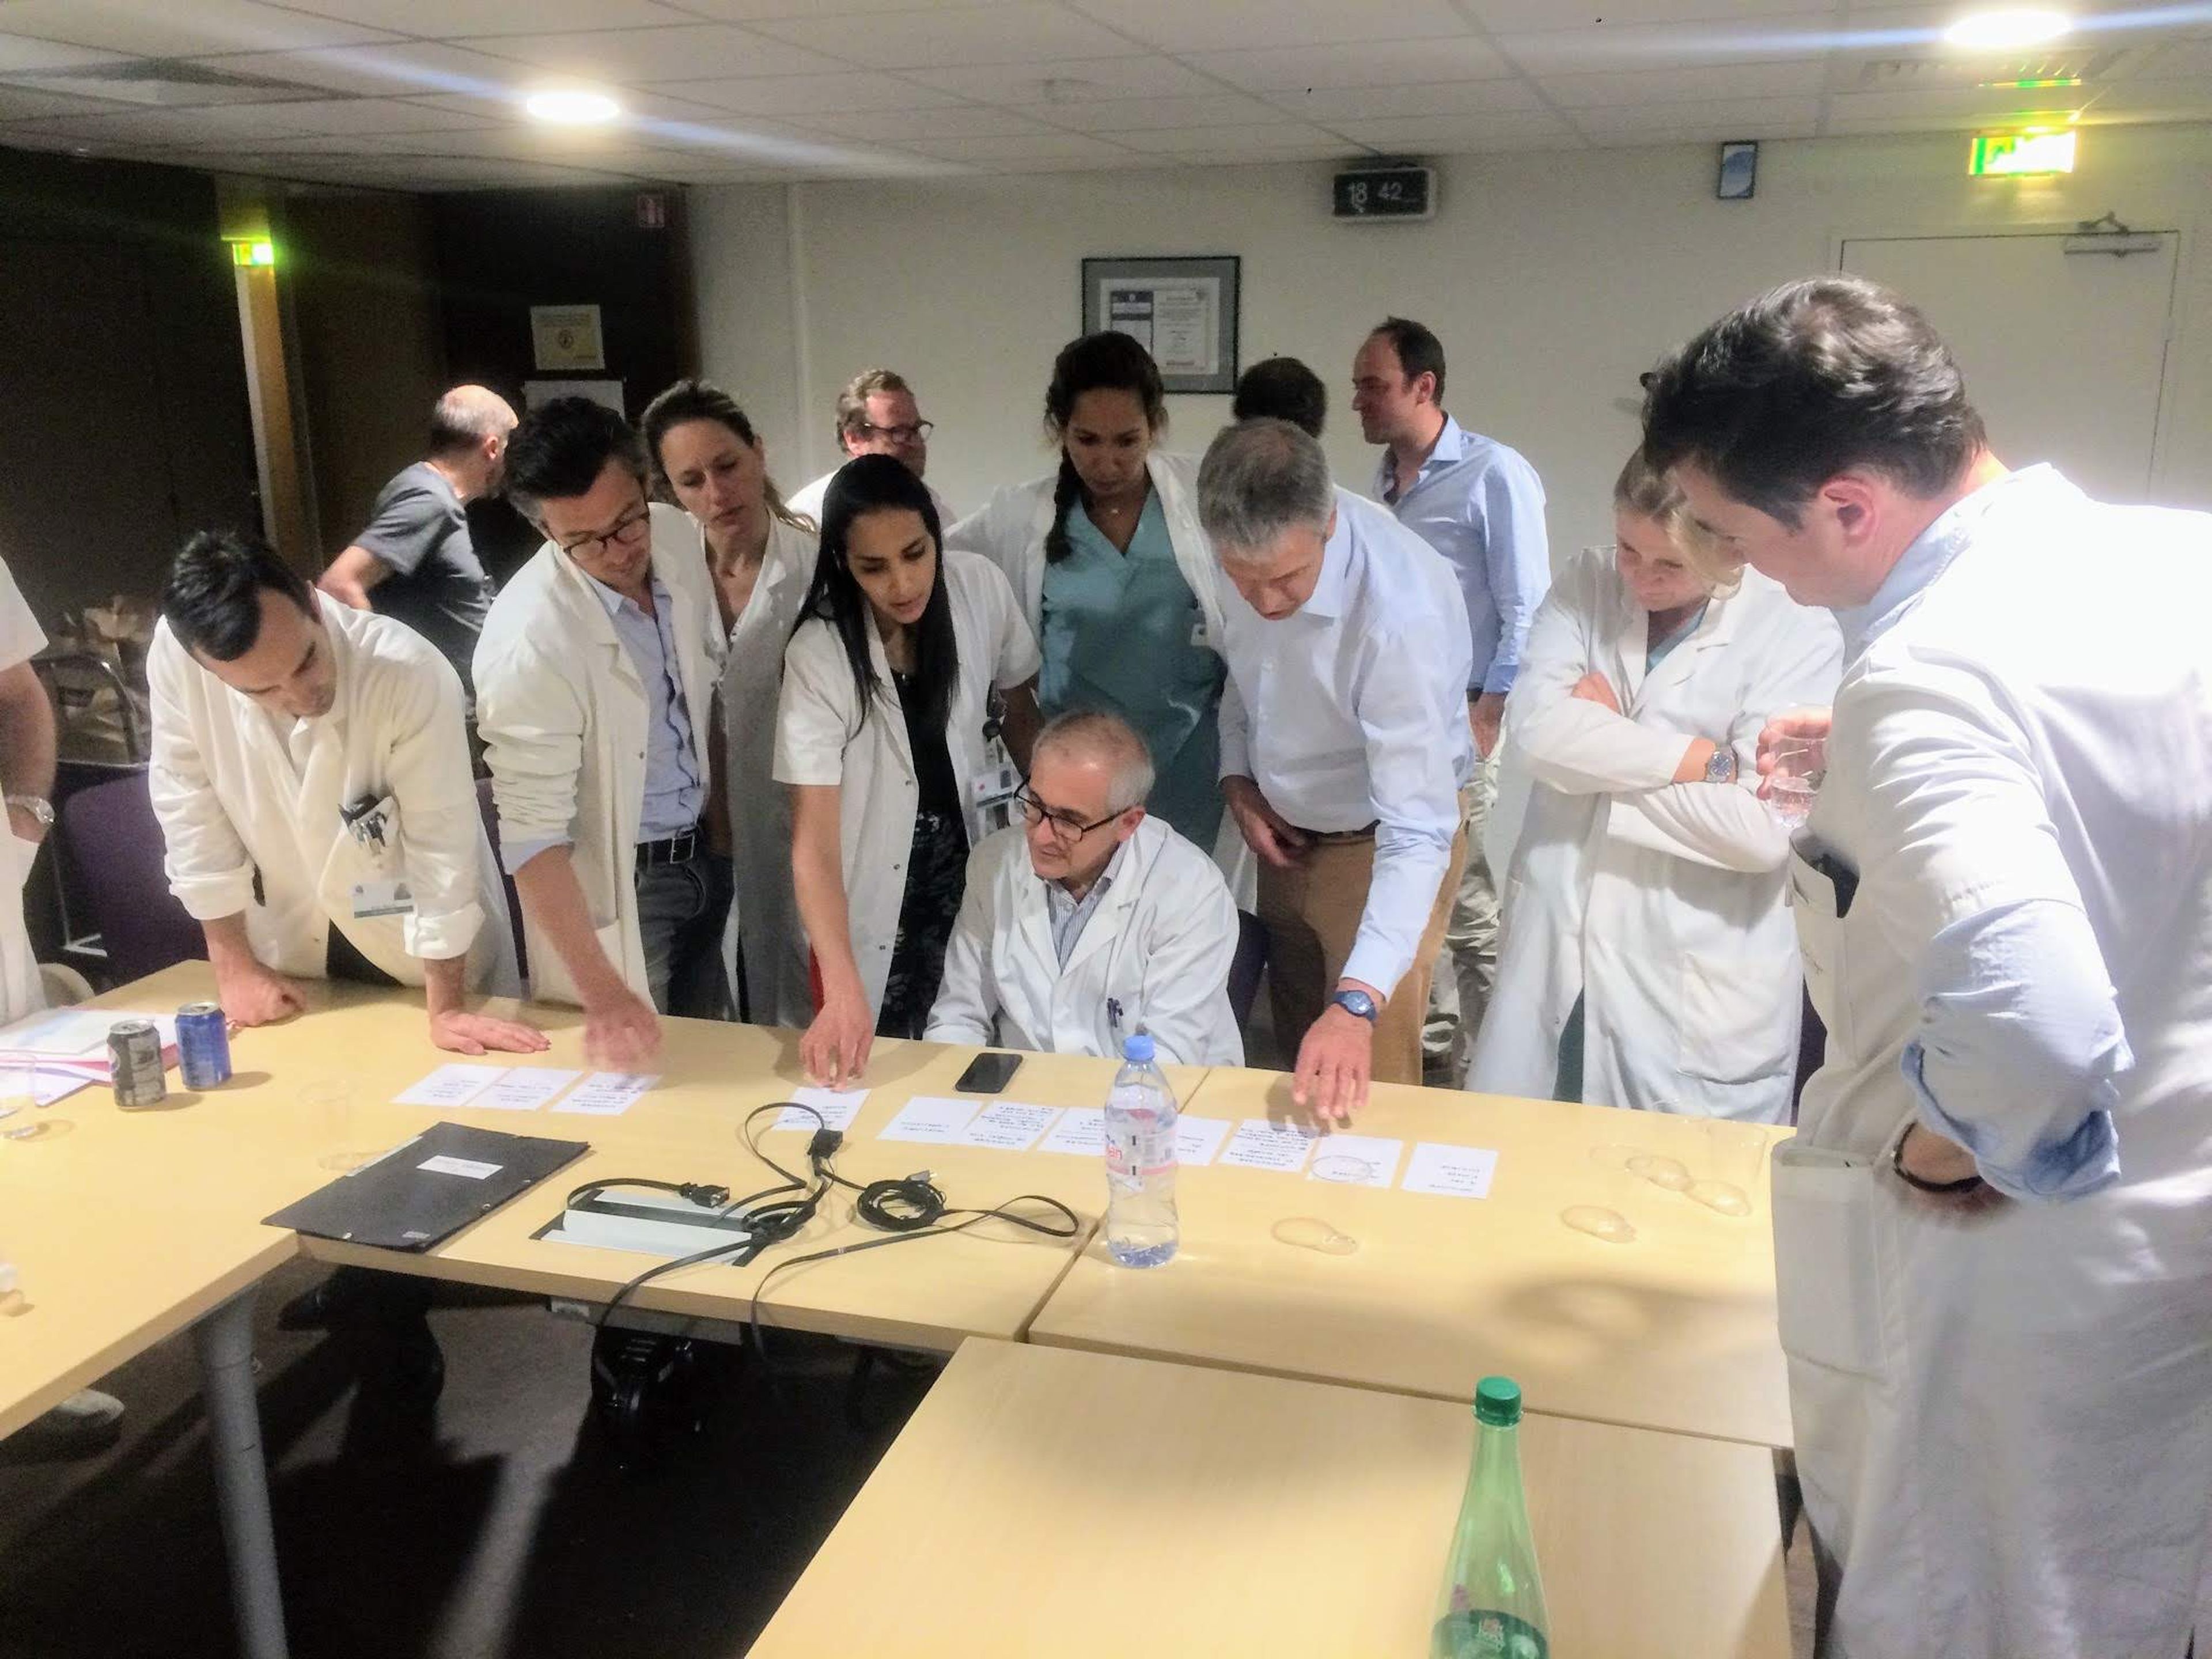

- Tras un reciente acuerdo, Incepto Medical proporcionará a varios hospitales de Madrid herramientas de IA para el diagnóstico y detección de enfermedades.

- Antoine Jomier, CEO de la empresa, explica a Business Insider España que el futuro de la sanidad pasa por esta tecnología: "Los médicos necesitan ayuda".

Desde la explosión de ChatGPT, la IA ha sido una fuente inagotable de noticias. Una de las últimas llega desde el sector de la salud: la empresa europea Incepto Medical acaba de firmar un acuerdo con los centros de Madrid de HM Hospitales para que estos puedan contar con sus servicios de diagnóstico asistido por IA.

El acuerdo supondrá para estos centros la implantación de la IA en la rutina diaria de diagnóstico por imagen y detección de patologías, así como la optimización los exámenes médicos por imagen a través de resonancia magnética, siempre con la última palabra del facultativo.

El objetivo es detectar enfermedades y lesiones con mayor precisión, eliminando, como explica la empresa en un comunicado, "el sesgo humano", si bien subrayan que "la labor de los profesionales seguirá siendo fundamental: todo informe elaborado por la IA debe ser suscrito por ellos".

Por ahora, 1.000 radiólogos de 130 clínicas , es decir, 100.000 pacientes al mes, ya utilizan un

sistema de IA que ya ha sido probado. Lo utilizaron científicos de la Universidad de Lund, en Suecia, en un experimento en el que se comparó el diagnóstico estándar del cáncer de mama y el diagnóstico apoyado por IA en más de 80.000 mujeres.

Publicado en The Lancet, las conclusiones del informe fueron que, aunque la tasa de detección de cáncer con el sistema estándar de doble lectura (dos radiólogos analizan las pruebas) y el sistema apoyado por IA fue similar, la carga de trabajo de lectura de pantalla se redujo un 44% en los sanitarios que pudieron apoyarse en la tecnología, con lo que su productividad aumentó.